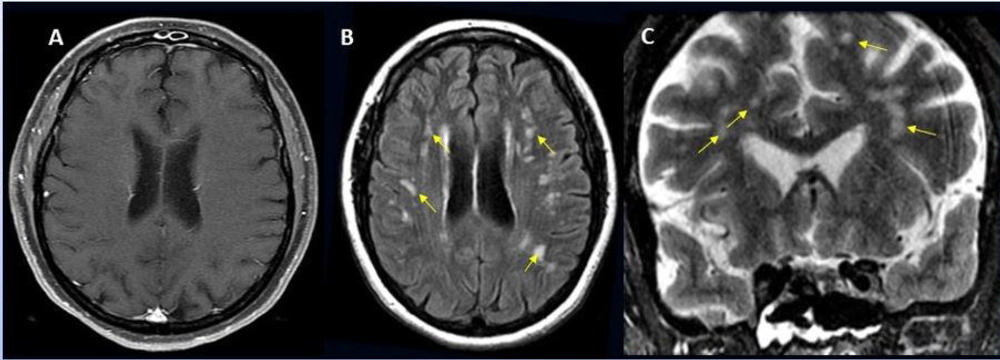

Acute anterior cerebral artery/middle cerebral artery watershed infarction seen in a 47-year-old male patient who presented with COVID-19 pneumonia. Image courtesy of RSNA

-

A 49-year-old female with past medical history of mitral valve disease and tricuspid valve regurgitation who developed headache followed by cough and fever presented to the ER with right upper eyelid ptosis (drooping). Courtesy of RSNA